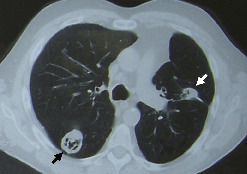

L’atteinte pulmonaire est variable : infiltrats alvéolaires, aspect en verre dépoli, nodules multiples excavés (fig. 9). L’hémorragie alvéolaire, complication majeure mais rare de la granulomatose avec polyangéite, se produit au niveau de la circulation pulmonaire distale entraînant un comblement alvéolaire (fig. 10). Elle se manifeste par une hémoptysie, une dyspnée, une anémie, des opacités diffuses alvéolaires et un liquide hémorragique au lavage bronchoalvéolaire (LBA). Des sténoses trachéo­bronchiques sont possibles.